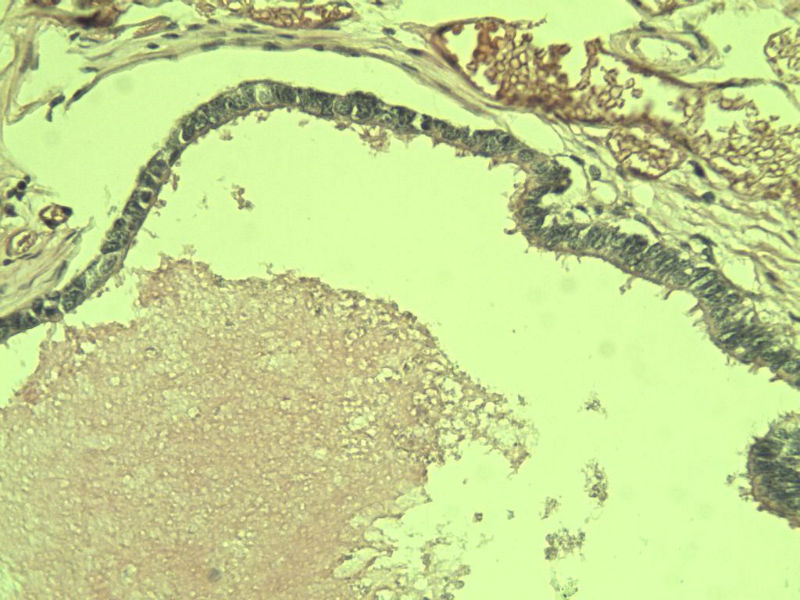

女性患者,42岁 阑尾 大体上看没问题 但是这些东西是什么?? 请指教,谢谢了!